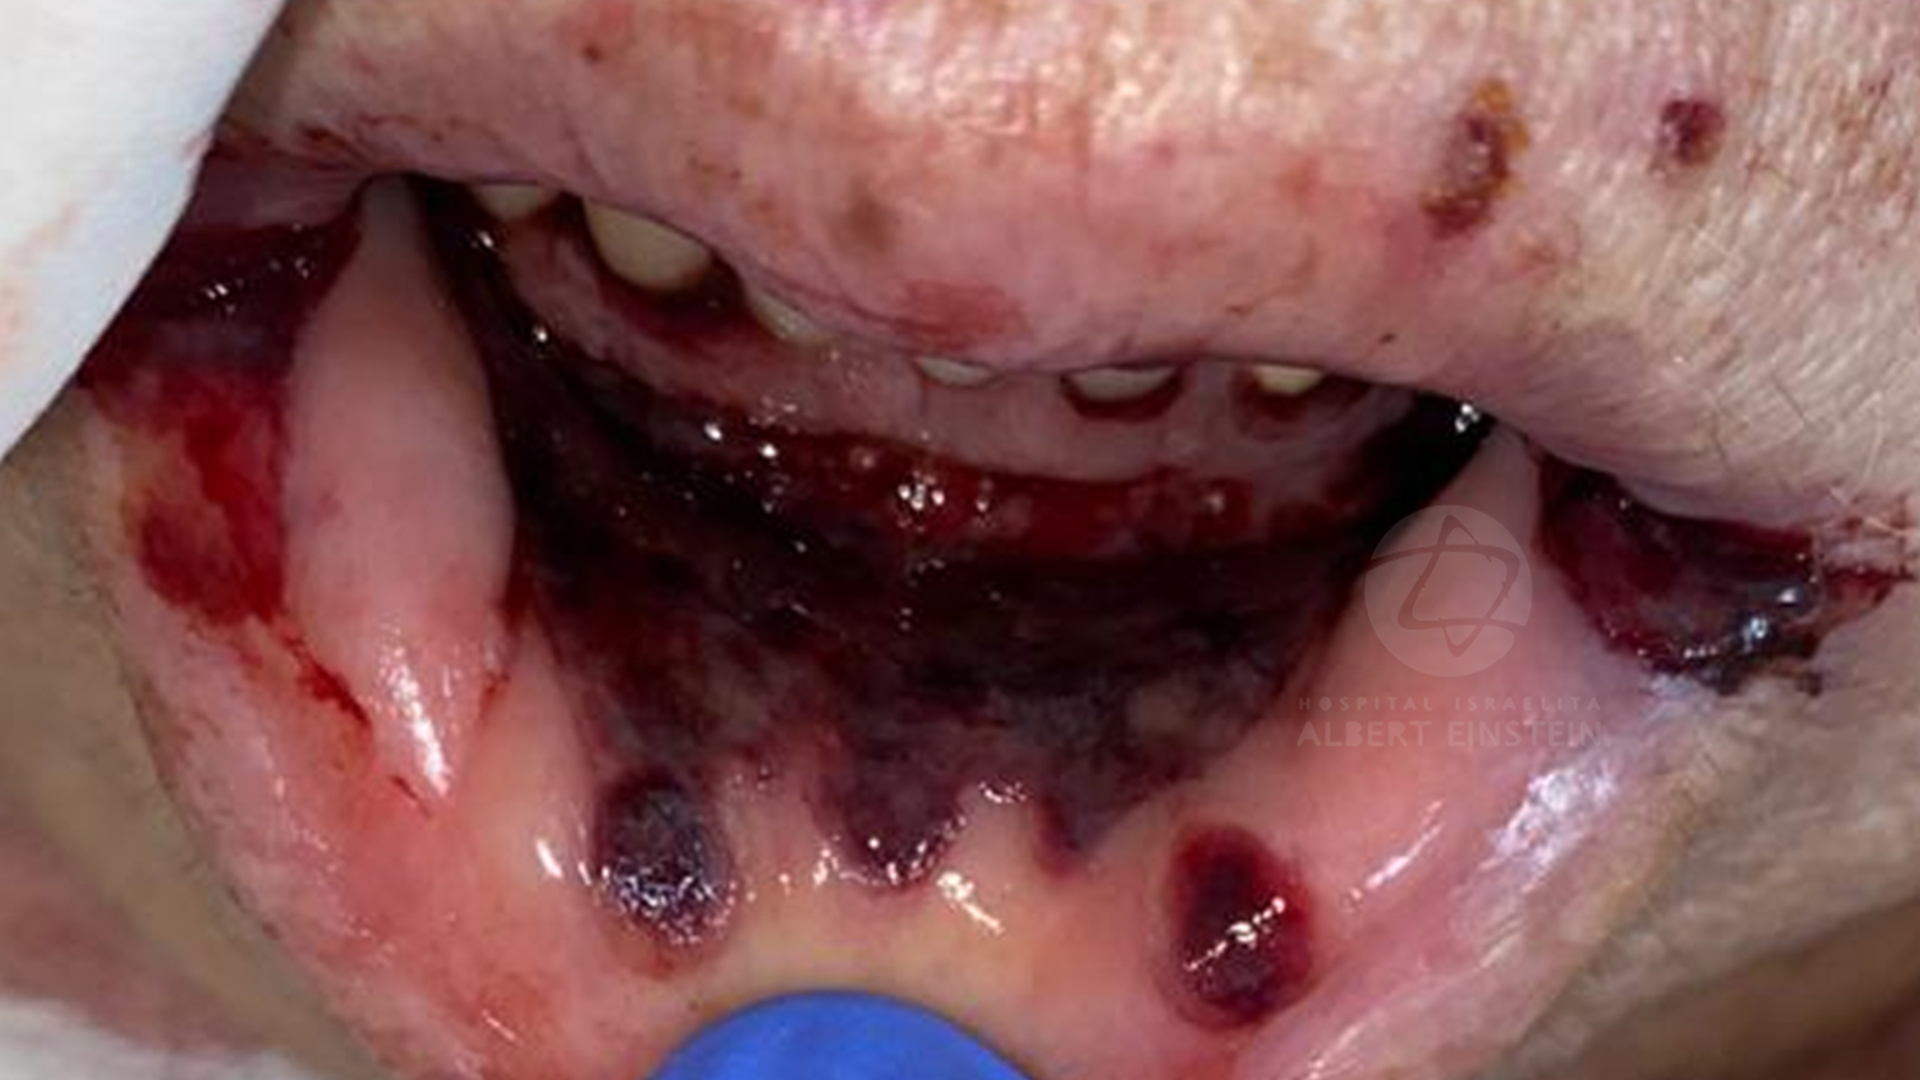

COVID-19 and oral cavity

Luciana Corrêa PhD, Associate Professor

Letícia Mello Bezinelli PhD, dentist of Hospital Israelita Albert Einstein

Fernanda de Paula Eduardo PhD, dentist of Hospital Israelita Albert Einstein